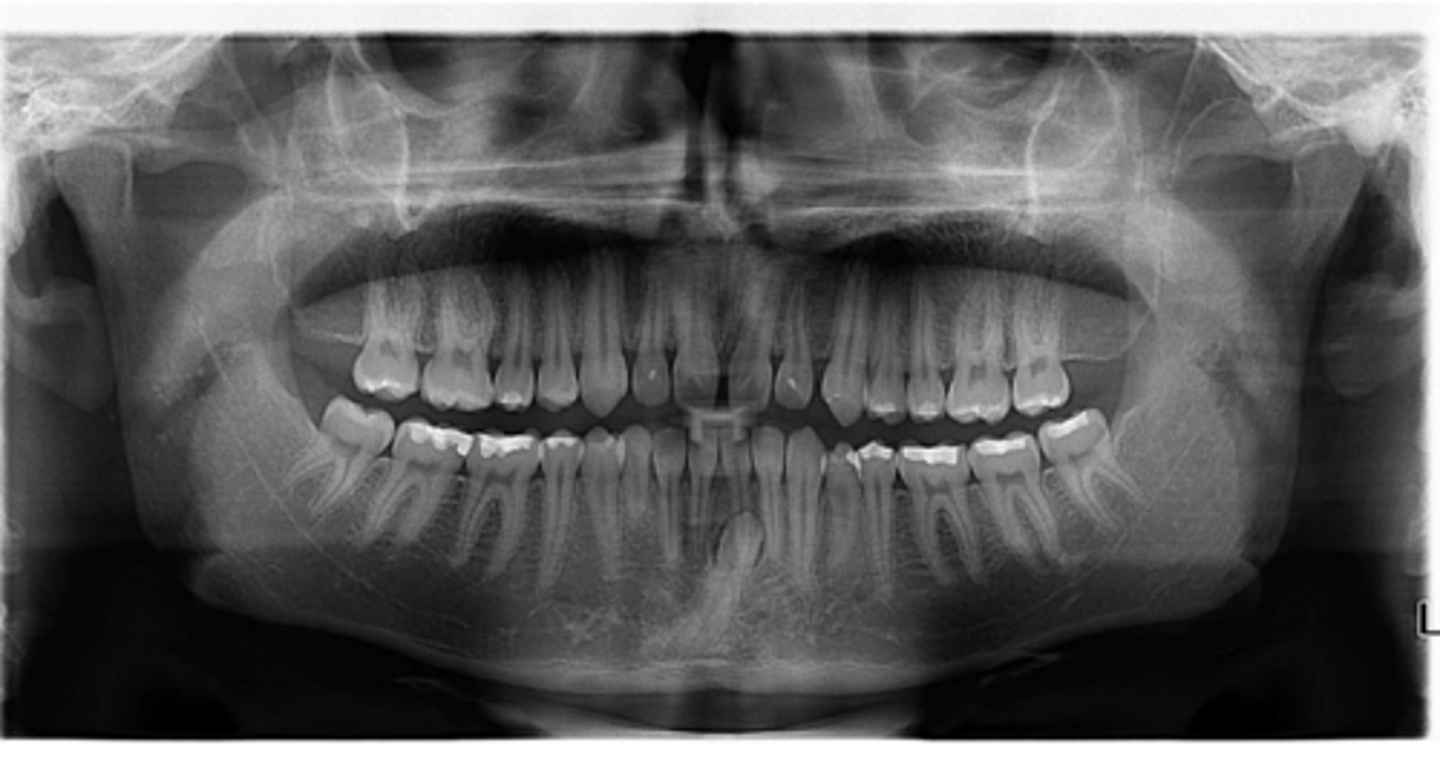

Right primary canine

Are there retained primary teeth?

Yes

Are there any impacted teeth?

Are the condyles symmetrical?

Is there a dilacerated root?

No

The mandibular left side has normal premolar/canine eruption, but the rigth side is abnormal.

Is the eruption pattern of this patient normal or not?

Are there any supernumerary teeth?

Are there any retained primary teeth?

Not at this stage

Are there impacted teeth?

Yes, within the range of normal

Symmetric condyles?

Yes - maxillary first molar

Dilacerated roots?

Yes - laterals

Are there congentially missing teeth in the maxillary arch?

Yes - an incisor

Are there congenitally missing teeth in the mandibular arch?

Yes - upper right near the premolar

Any impacted teeth?

Can't see, so can't say

Yes - #2, also #27?